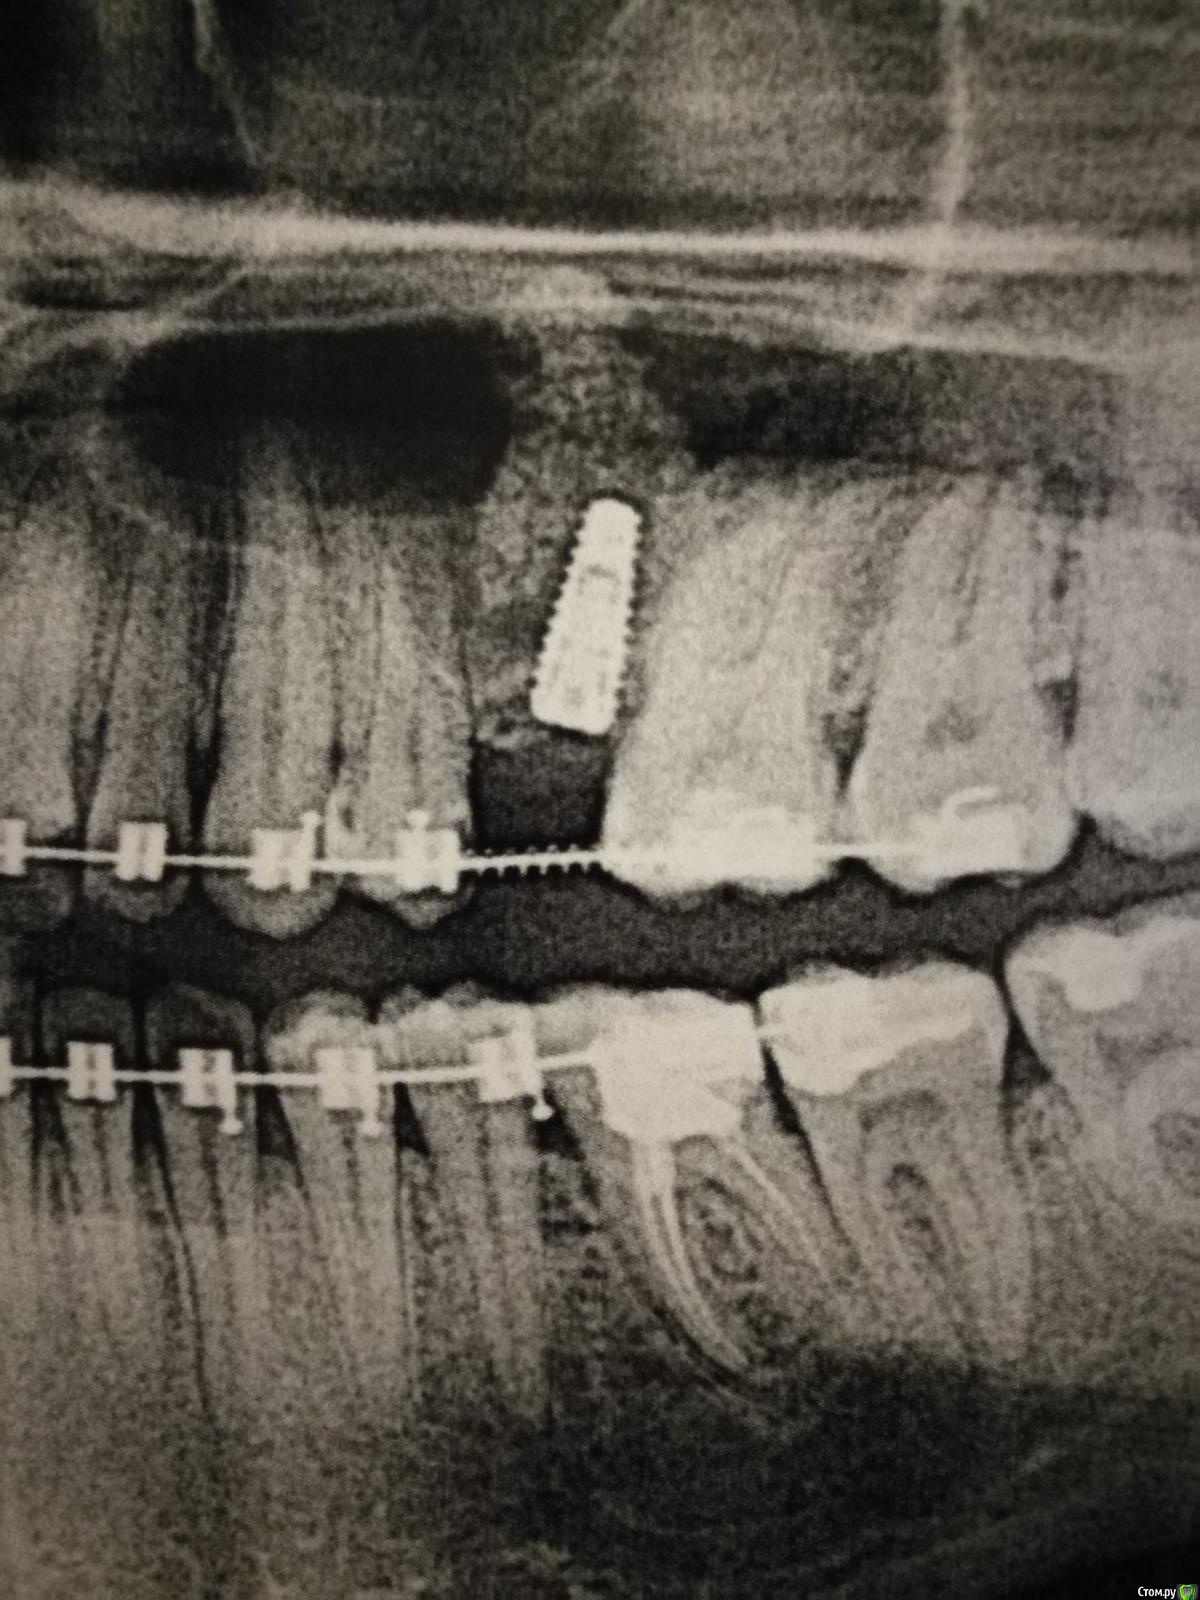

Nadin1 Опубликовано 23 декабря, 2018 Поделиться Опубликовано 23 декабря, 2018 (изменено) Здравствуйте! Нужна ваша консультация. 17 декабря был сделан открытый синус лифтинг и одномоментно установлено 2 импланта. Меня беспокоит не слишком ли близко к корню зуба установлен имплант? Мой хирург говорит, что нормально. Снимки прикрепляю. Спасибо. Изменено 23 декабря, 2018 пользователем Nadin1 Ссылка на комментарий

АнтонТЛТ Опубликовано 23 декабря, 2018 Поделиться Опубликовано 23 декабря, 2018 Нормально 5 Ссылка на комментарий